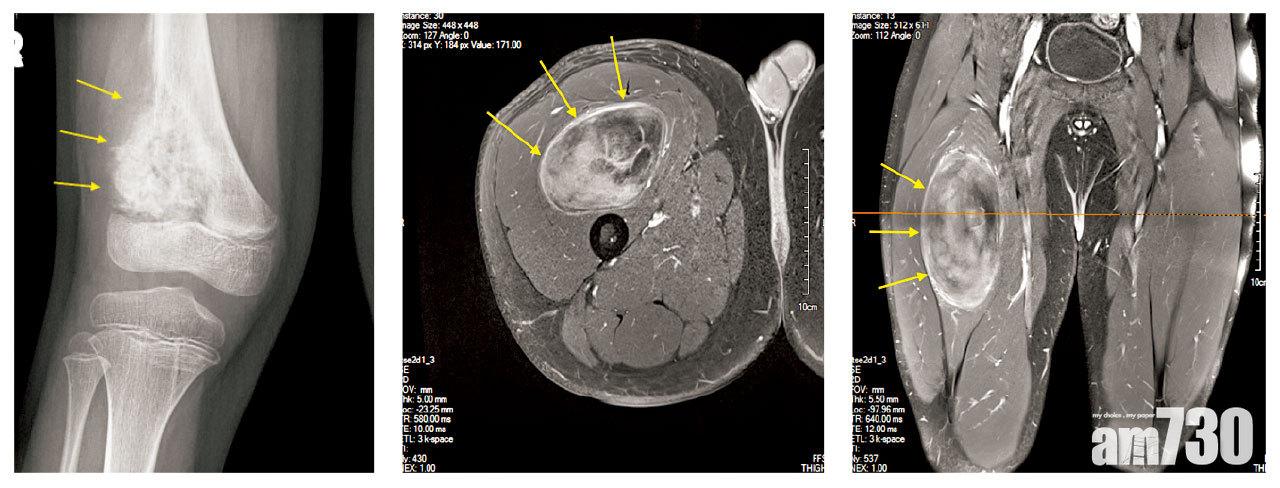

蘇鎰昌建議,要正確診斷骨骼肉瘤及軟組織肉瘤,跨專科團隊包括骨科(腫瘤)醫生、放射診斷醫生及病理科醫生,都要對此症有充足認知,並緊密溝通與合作;當有可疑腫塊,應作進一步影像診斷如磁力共振、正電子掃描等,「做活檢亦應先制訂手術計劃,因萬一確診肉瘤,手術亦須於活檢同一傷口處開刀,減低擴散風險外,亦確保手術安全和有效。」

六十多歲的Ava,兩年前發現自己膝蓋上方內側有小腫塊,向普通科醫生求診,醫生認為是良性腫瘤,轉介至公立醫院,但要排期一年。Ava為更早確定病情,向外科專科求診,醫生照超聲波及磁力共振後,認為是良性靜脈腫瘤,安排手術切除。但手術中途,醫生發現腫瘤可能為惡性,最後切除部分腫瘤後中止手術,而病理報告亦確定為惡性腫瘤。Ava擔心癌細胞擴散,也害怕需要截肢,再向不同醫生求診,最後在兩個治療方案間,決定先接受5個星期電療,再以廣泛切除手術治療,現已切除整個肉瘤,康復進展良好。